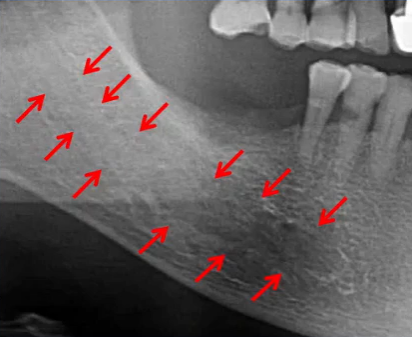

下颌种植主要判断:神经管走行及位置

左侧神经管下壁显示清晰,但上壁右侧神经管不清晰,前段疑似膨大。

神经管位于46、47位置膨大,上壁不清。